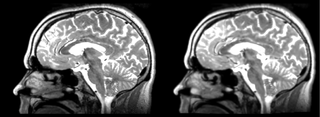

Original file(1,162 × 426 pixels, file size: 323 KB, MIME type: image/png)

Registration of a t2w image to arbitrary t1 and back via BSpline Registration module.

current15:07, 21 April 2009Thumbnail for version as of 15:07, 21 April 20091,162 × 426 (323 KB)Rauscha (talk | contribs)Registration of a t2w image to arbitrary t1 and back via BSpline Registration module.